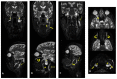

In the present study, through a case series, we highlighted the role of magnetic resonance (MR) in the identification and diagnosis of peripheral neuropathies. MR neurography allows the evaluation of the course of nerves through 2D and 3D STIR sequences with an isotropic voxel, whereas the relationship between nerves, vessels, osteo-ligamentous and muscular structures can be appraised with T1 sequences. Currently, DTI and tractography are mainly used for experimental purposes. MR neurography can be useful in detecting subtle nerve alterations, even before the onset of symptoms. However, despite being sensitive, MR neurography is not specific in detecting nerve injury and requires careful interpretation. For this reason, MR information should always be supported by instrumental clinical tests.